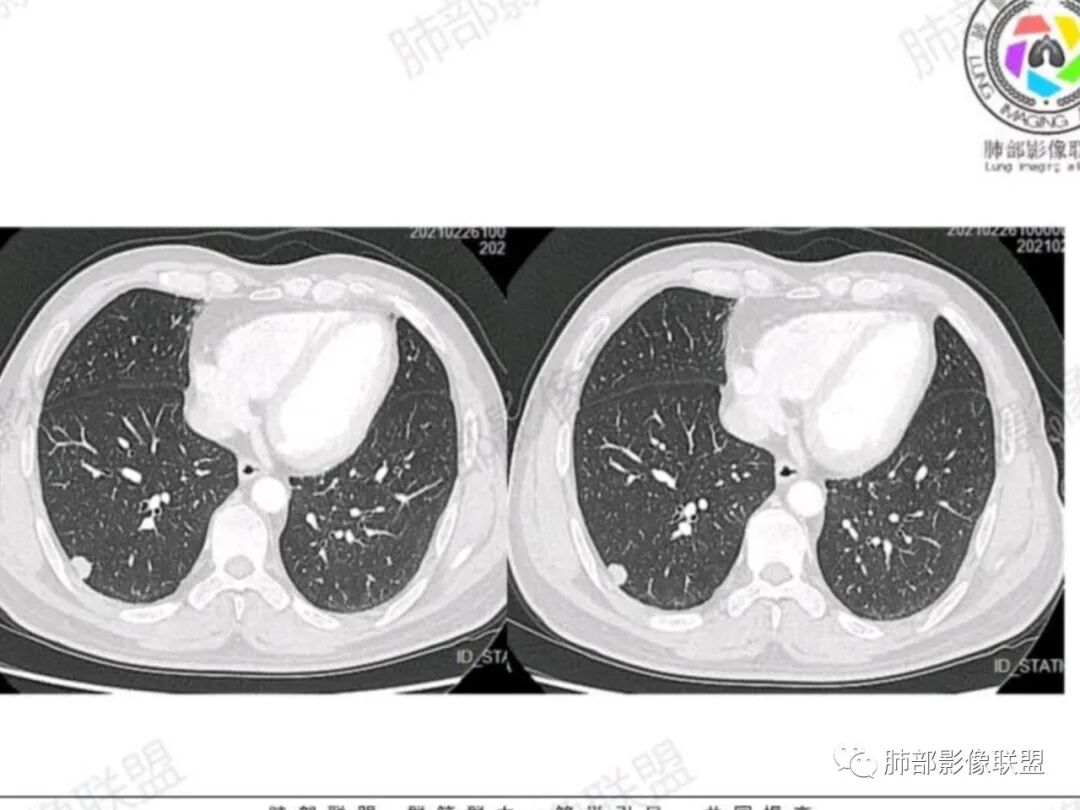

右肺下叶胸膜下实性小结节,呈条状,长轴平行胸膜,宽基底与胸膜相贴,病灶边缘毛糙,胸膜侧可见U型凹陷,轻度牵拉胸膜,平扫密度均匀,增强扫描后中度强化,单发孤立性结节,中年男性,体检发现,建议先隐球菌荚膜实验,阴性考虑腺癌可能性大,必要时建议短期随访,

右肺下叶胸膜下实性山丘状结节影,密度均匀,边缘可见棘状突起,结节胸膜侧收缩,见胸膜凹陷征。周围无磨玻璃及卫星病灶,增强后结节轻-中等强化。考虑腺癌可能,肉芽肿性炎待排。

老年男性,右肺下叶胸膜下孤立实性结节,边缘平直凹陷+膨隆,胸膜下脂肪间隙增宽,空洞型胸膜凹陷,中度较均匀强化,与支气管关系不明确。考虑炎性肉芽肿>癌

男性,53岁,体检发现右肺下叶胸膜下小结节,整体膨隆,宽基底与胸膜相连,不均匀强化,内部似见坏死区,局部层面似见小尾巴,考虑恶性可能,腺癌或小细胞

右肺下叶后基底段胸膜下实性结节,病灶边缘毛糙,胸膜侧可见凹陷,内侧缘膨隆,轻度牵拉胸膜,增强扫描后中度延迟强化,考虑腺癌,鉴别隐球菌

中年男性,查体发现,右肺下叶孤立实性结节,有膨隆,边缘稍光滑,长轴与胸膜平行,似山丘征,胸膜下脂肪间隙清晰,密度较高,轻度强化,无坏死,恶性考虑小细胞肺癌?良性结节考虑SFT,肉芽肿等。

中老年男性,体检发现,右肺下叶胸膜下结节,浅分叶、毛刺,均匀强化,考虑恶性

男,63,体检发现肺部结节。胸部CT:右肺下叶胸膜下类圆形实性结节影,边界清楚,边缘膨隆、短毛刺,细支气管在病灶边缘截断,小血管进入,胸膜牵拉圆洞样凹陷,胸膜外脂肪间隙增宽。增强密度不均匀,内有点状低密度。引流区域淋巴结增大?考虑恶性,腺?小?鉴别PC、TB等肉芽肿。

右肺下叶胸膜下结节,膨隆为主,细小毛刺,增强静脉期较动脉期变化不大,密度不均匀,体检发现,邻近胸膜有牵拉,重建呈圆洞样改变,良恶性征象都有,老年人,孤立结节,按恶性对待,腺癌或转移瘤>炎性肉芽肿,建议穿刺活检

右下实性结节,膨隆,有毛刺,强化不甚明显,胸膜下脂肪间隙清,重建空洞样改变,良恶性征象皆有,恶性对待,建议穿刺活检

腺癌,不鉴别(靠肺内侧明显膨隆,毛刺,胸膜侧凹陷,两端与胸膜接触处有微积液,胸膜接触面无增厚,增强中度强化),收缩力相对偏弱,病理类型可能是腺泡为主,也可能是结节型粘液腺癌。